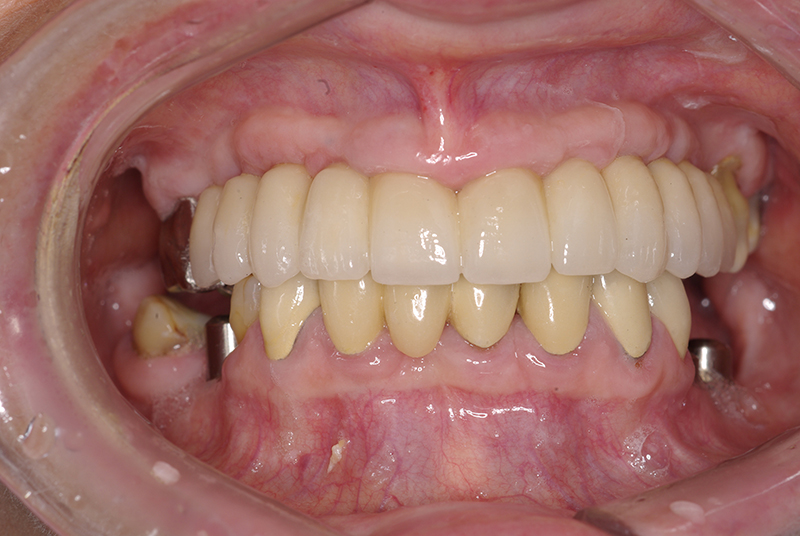

Na Clínica Pontes Odontologia, somos referência em implantes dentários em Fortaleza, oferecendo tratamentos de alta qualidade e tecnologia de ponta. Os implantes dentários são estruturas de titânio posicionadas cirurgicamente no osso maxilar ou mandibular para substituir as raízes dos dentes ausentes. Essa técnica permite a fixação de próteses personalizadas, restaurando a função mastigatória, a estética e a autoestima dos nossos pacientes.

Utilizamos a tecnologia CAD CAM, um sistema avançado que possibilita a confecção precisa das próteses dentárias diretamente sobre os implantes. Esse método inovador garante um ajuste perfeito, um resultado estético superior e proporciona muito mais conforto e durabilidade. Com o CAD CAM, nossos pacientes contam com um processo mais rápido e previsível para alcançar o sorriso desejado.